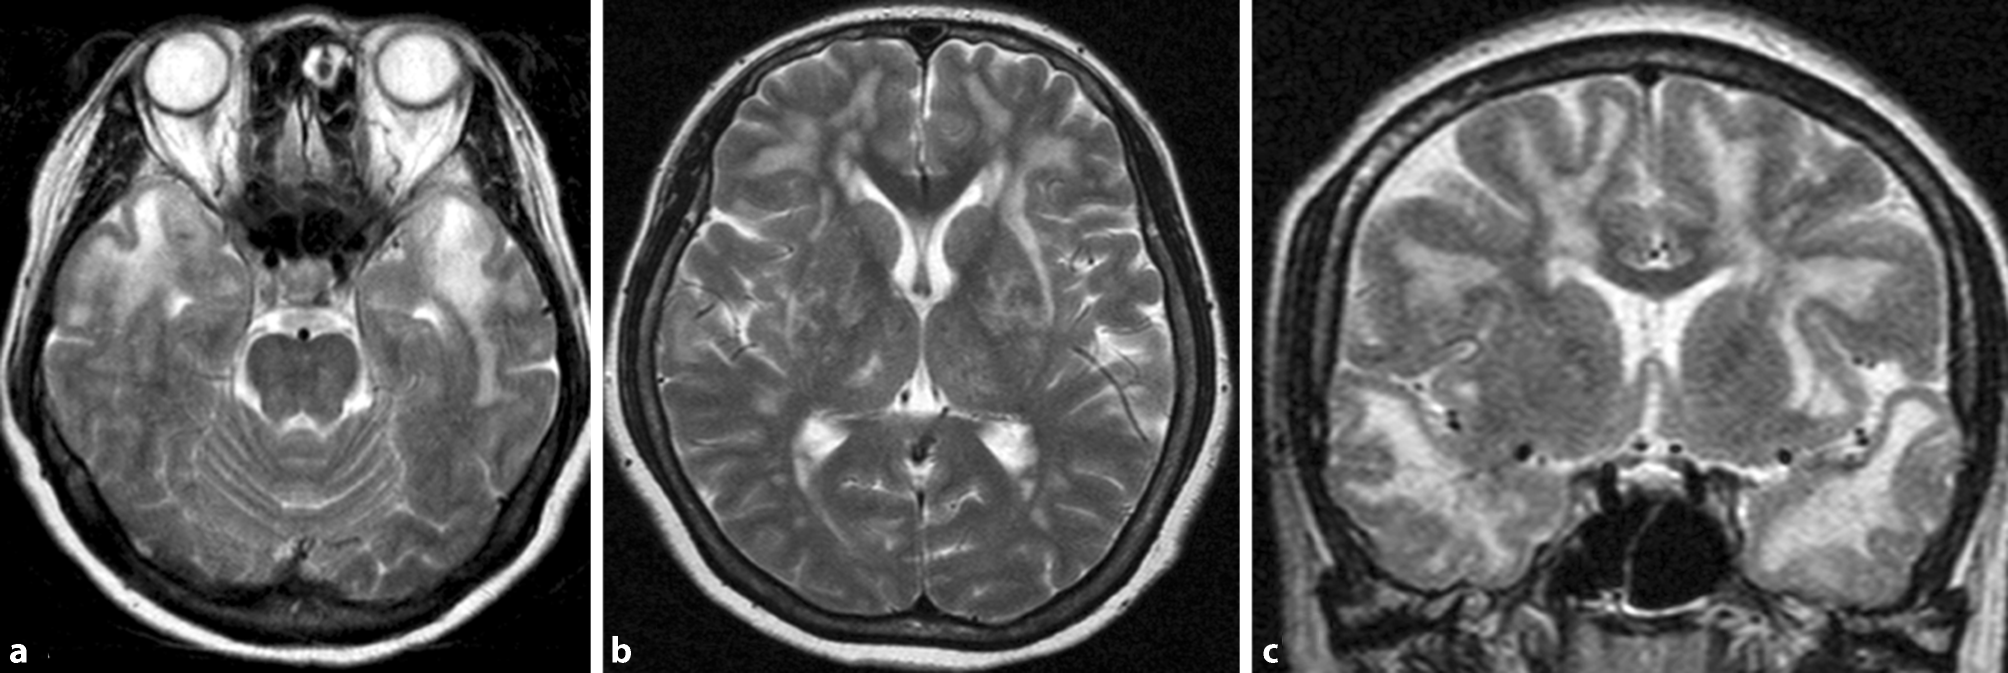

Lacunes and Virchow-Robin spaces

Lacunes are deep, small-vessel infarcts with a CSF-like signal on all MRI sequences (illustrated in Fig. 5). In contrast, Virchow-Robin spaces are enlarged perivascular spaces usually due to volume loss of the surrounding tissue with a predilection for the basal ganglia (illustrated in Fig. 6).

Fig. 6

Virchow-Robin spaces. Illustration of enlarged Virchow-Robin spaces (circles) in the lower aspect of the basal ganglia on both sides on axial T2-weighted images

Bild vergrößern